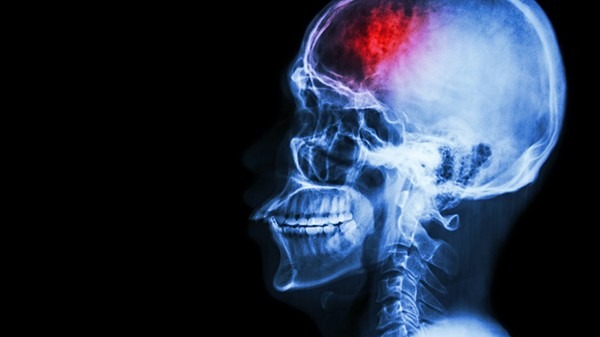

脑卒中主要分为两种,一是各种原因造成的急性堵塞,被称为脑缺血。一种是脑血管急性出血,被称为脑出血。虽然两者都是血管出了问题,但在干预治疗上却完全不同。

脑缺血是由于脑中血管的闭塞导致血流不通,医生通常利用溶栓、取栓等治疗手段将血管打通。脑出血是由于血管壁的破损使血流到脑子里形成血肿,血液里的铁元素等物质破坏了周围正常的组织。这时就要通过手术将血肿吸出,有些血肿较大,在短时间内形成对正常结构的压迫。这时候即使把血肿吸出,也可能对神经功能造成严重的损伤。所以在治疗时间上都是需要争分夺秒的。

脑缺血的患者有4.5小时的黄金救治时间,医生在这个时间内将血管疏通。血液流通后,脑组织还能救活,只要后续治疗、护理跟得上,患者康复的几率非常大。而脑出血发病更加个体化,出血的部位、大小对病情的影响和干预的时间都不一样。治疗也比脑缺血要负责,因此治疗上没有黄金时间,更强调越快越好。